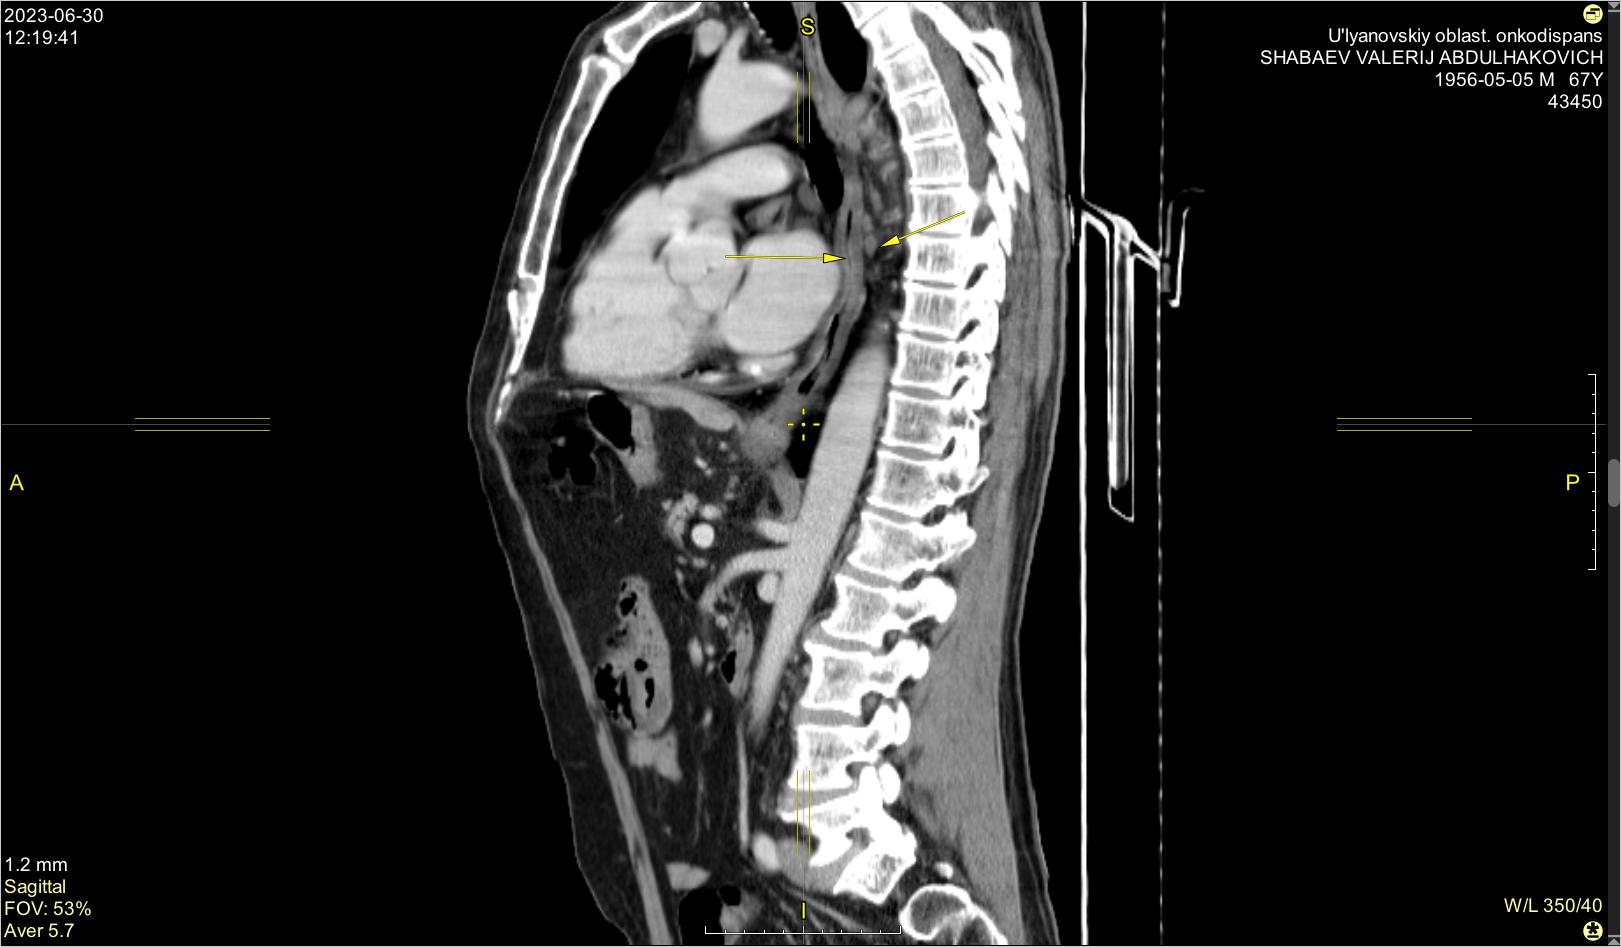

Материал и методы. Представлено 3 клинических случая одновременного развития плоскоклеточного рака пищевода и аденокарциномы желудка у пациентов, получавших лечение в ГУЗ «Областной клинический онкологический диспансер», г. Ульяновск, и ГАУЗ СО «Свердловский областной онкологический диспансер», г. Екатеринбург. Пациентам проведены хирургическое вмешательство, химиотерапия и лучевая терапия.

Результаты. Первично-множественный синхронный плоскоклеточный рак пищевода и аденокарцинома желудка представляют собой сложную клиническую задачу, требующую вмешательства мультидисциплинарной команды специалистов. Химиолучевая терапия с использованием схемы FOLFOX продемонстрировала хорошую переносимость и позволила достичь удовлетворительного клинического ответа со стороны опухолей обеих локализаций.